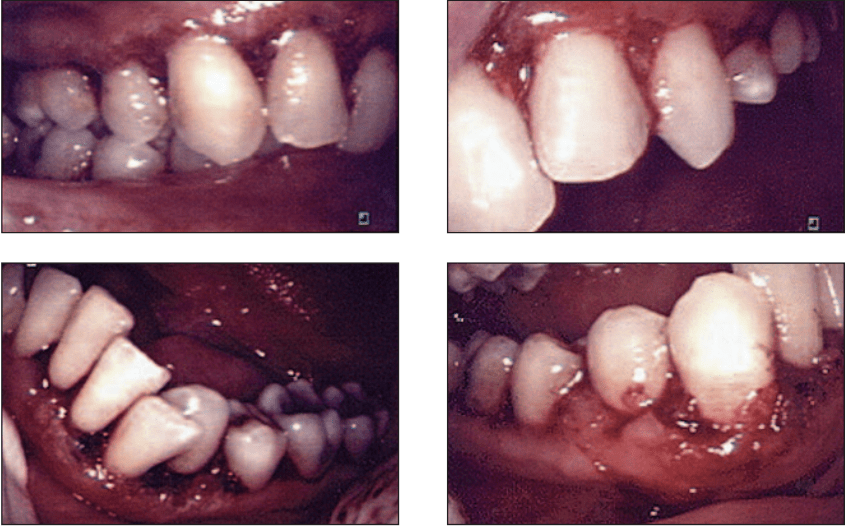

Oral and mucosal conditions in animals—such as ulcers, stomatitis, gingivitis, and periodontal inflammation—are often chronic, painful, and difficult to manage with conventional treatments. Veterinary cold laser therapy has emerged as a groundbreaking, drug-free alternative that […]

In today’s veterinary practice, non-invasive and effective treatment options are more essential than ever—especially for common but serious issues like gingivitis, tumors, and skin lesions in pets. These conditions can cause pain, disrupt daily routines, […]

Periodontal disease is a widespread chronic condition that affects millions globally. Characterized by gum inflammation, bone loss, and risk of tooth loss, it poses significant treatment challenges for dental professionals. Diode lasers have recently emerged […]

Gum disease, or periodontal disease, affects millions globally. If untreated, it can lead to tooth loss and bone degradation. Traditional treatments like deep cleaning and surgery are often invasive and uncomfortable. Fortunately, innovations in dental […]

Modern dentistry is increasingly relying on advanced technology to improve patient outcomes, and one of the technologies driving this trend is the soft tissue diode laser, particularly in sulcular debridement. This procedure, performed mostly by […]